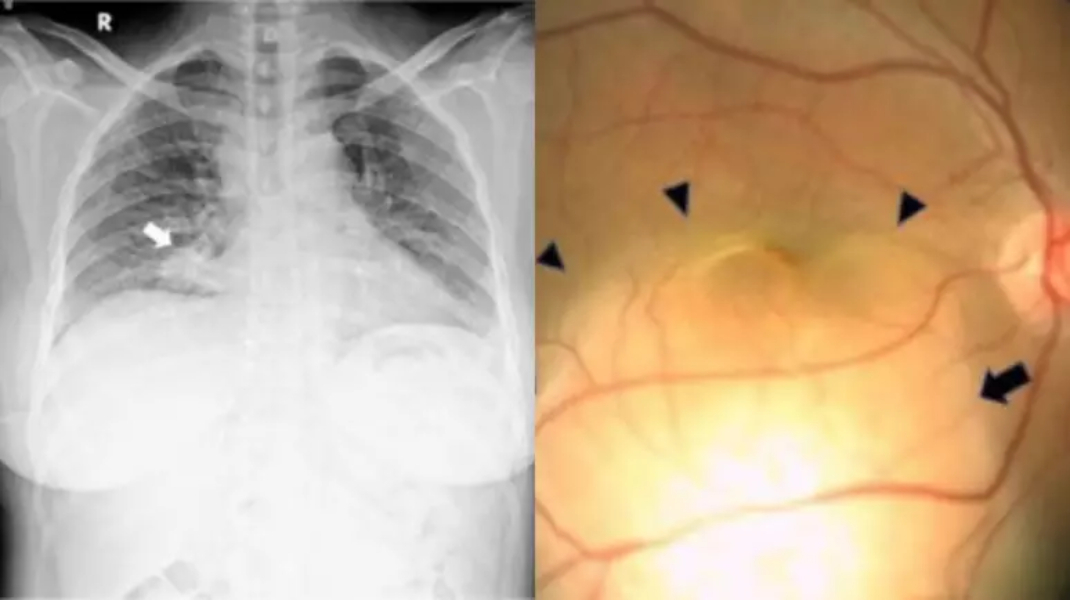

Foto mostra Raio X do tórax e exame ocular feitos na paciente | Foto: Reprodução/Elsevier

Caso- O estudo de caso foi publicado na edição de julho da revista Radiology Case Reports (Relatos de casos de Radiologia). Após os exames, foi encontrada uma grande lesão abaixo da retina do olho direito e uma lesão semelhante e menor, no olho esquerdo. A paciente passou também por um raio-x do tórax que mostrou um nódulo na zona inferior do pulmão direito, que os médicos suspeitaram ser cancerígeno.

Exames- Após realizar outros exames, foram encontrados tumores em diversos órgãos de seu corpo e ela foi diagnosticada com carcinoma de pulmão com metástase de coroide (membrana que envolve o olho) em ambos os olhos. Conforme o estudo, esse tipo de câncer se desenvolve nos olhos em cerca de 0,1% a 7% dos casos de câncer de pulmão metastático.